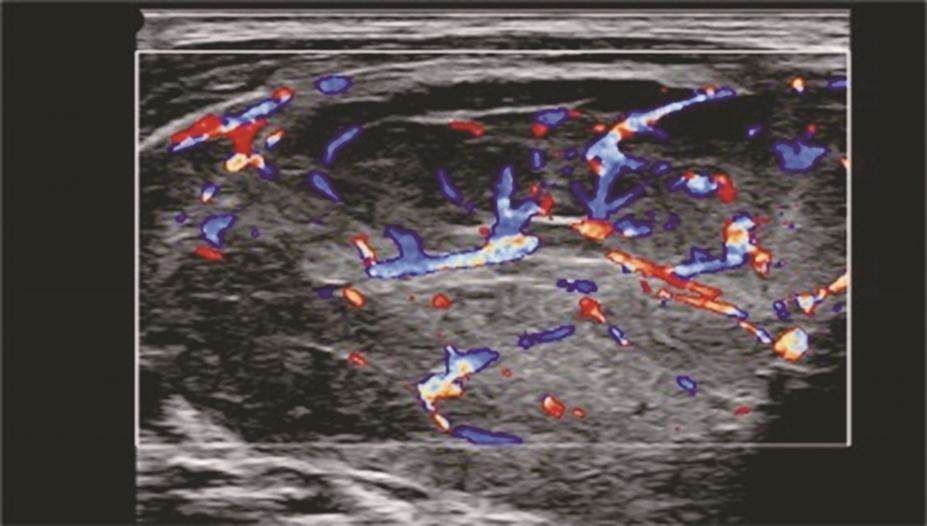

(十一)甲状腺髓样癌

甲状腺髓样癌超声上多为不规则低回声实性结节,内部回声不均,部分病例可伴有囊性成分,髓样癌丰富的血流信号是其超声主要特点。约1/3的髓样癌超声表现不典型,除了血供丰富表现外,类似良性结节(图13、图14)。

图13左侧颈部纵切面:甲状腺左叶中部中低回声(箭头所示),分叶状,可见囊性成分及点状强回声(微小钙化)

图14左侧颈部纵切面(与图3-3-13同患者、同切面):甲状腺左叶中部中低回声内部彩色多普勒血流信号丰富而杂乱